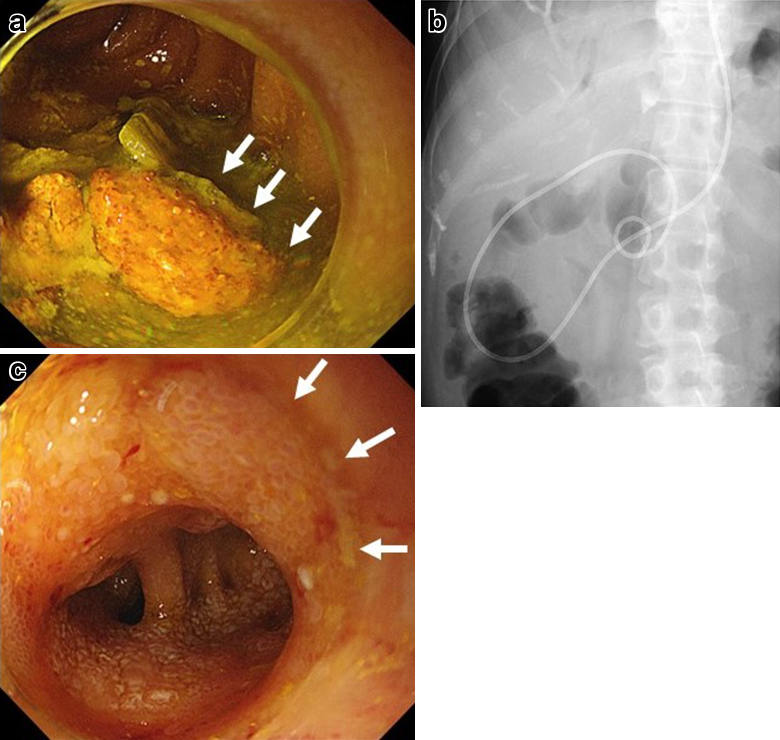

経過:繰り返す胆管炎の臨床的経過,および腹部造影CTでの挙上空腸の囊状拡張の所見から,挙上空腸に何らかの通過障害が疑われたため,ERCPを施行した.胆管空腸吻合部近傍の挙上空腸に狭窄を認めたものの,胆管空腸吻合部まで内視鏡は到達可能であった.胆管空腸吻合部には明らかな狭窄は認めなかったが,胆管空腸吻合部より盲端側の挙上空腸は著明に拡張し,腸管内に腸石,および胆石を認めた(Fig. 2a).以上より,挙上空腸の狭窄に伴う急性胆管炎の可能性を考え,挙上空腸内に内視鏡的胆道ドレナージ(endoscopic nasobiliary drainage;ENBD)用の6Frチューブを留置し,その後速やかに胆管炎は軽快した(Fig. 2b).しかし,ステント挿入1週間後にステント閉塞による急性胆管炎が再燃したため囊状拡張した挙上空腸を経皮的に穿刺ドレナージを行った.この時のドレーン造影では,拡張した挙上空腸内から肛門側腸管内への造影剤の排出は認められなかった(Fig. 3).ERCP施行時,胆管空腸吻合部から左右肝管二次分枝まで広範囲にわたって胆管上皮にびまん性の大小不同の顆粒状粘膜を認めており(Fig. 2c),さらに入院時の腹部造影CTを見直すと,挙上空腸の狭窄部は肝門部に集束するようにひきつれ,狭窄しており,癌による浸潤と考えた.また,肝十二指腸間膜内には腫大したリンパ節を認めた(Fig. 4a~f).左右肝管,および肝門部胆管上皮から生検を施行したところ,病理学的検査にて腺癌と診断された(Fig. 5a~c).以上より,切除不能肝門部胆管癌,T4aN1M0 stage IVAと診断した.

a) Endoscopic findings revealed bile duct stone and enterolith in the jejunal limb. b) An endoscopic naso-biliary drainage tube was placed in the dilated jejunal limb. c) Granular mucosa of the bile duct was observed diffusely from the choledocho-jejunal anastomosis to the distal side of the bilateral secondary branches of the hepatic duct.

Infusion of contrast medium to the proximal jejunal limb identified dilatation, but the medium was not discharged to the distal side of the jejunal limb.